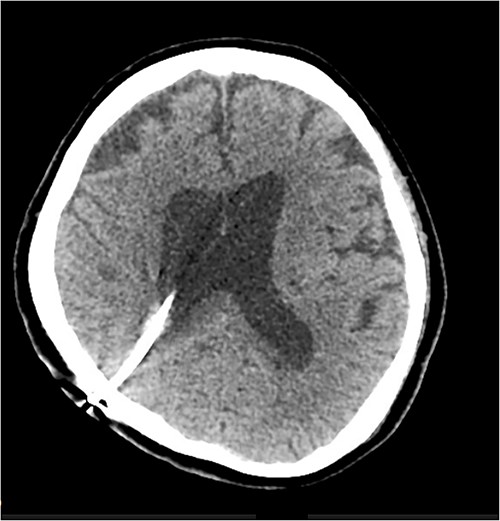

On clinical review after the shunt revision, the patient’s level of consciousness had improved, with her Glasgow Coma Scale returning to 15. She was alert and conversational in both English and her native language, and was moving all limbs (although her pre-existing right hemiparesis persisted). A repeat CT brain was performed 1 day postoperatively which showed resolution of the cyst and reduced midline shift from 4 to 3 mm. An additional CT was performed 8 days after the revision, which revealed further improvement with reduced oedema and almost completes normalization of the midline shift to 1 mm. The patient was subsequently returned to the rehabilitation department for ongoing therapy and discharge planning. A progress CT done 41 days after the shunt revision showed no further evidence of the cyst, although ventricular dilatation persisted (Fig. 3).

CT scan performed 41 days after shunt revision, showing resolution of the periventricular cyst.